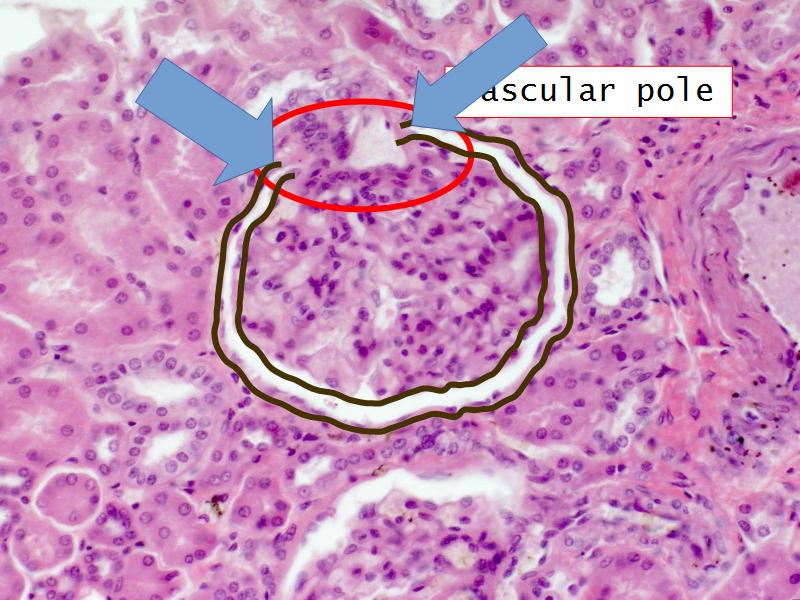

- The renal corpuscle

- Make an annotated diagram of a nephron, including the juxtaglomerular apparatus. Indicate the flow of blood and water in each part, and how solutes are filtered, secreted and reabsorbed.